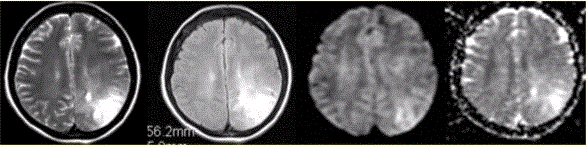

问题 女性,42岁。癫痫1个月,近期加重。无发热,无其他病史。MRI表现如下图。 有关该病MR表现,描述正确的是

选项 A.左侧顶叶不规则形长T2信号影,边界清晰 B.病变占位效应明显 C.DWI和ADC显示病变均呈高信号,提示病变的T2效应 D.病变邻近珠网膜下腔增宽 E.病变邻近脑膜增厚

答案 C